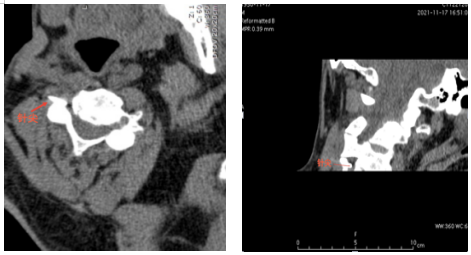

经人介绍,李爹爹来到了91porn 疼痛科二病区就诊,杨庆红主任经过查体后诊断其为带状疱疹性神经痛,疼痛范围为颈丛神经分布区域。李爹爹住院后,医生予以口服普瑞巴林胶囊及泰勒宁止痛,但效果不佳,后进行了超声引导下颈丛神经阻滞,但效果维持时间不长,最终杨庆红主任决定为患者施行CT引导下颈丛神经脉冲射频微创手术。但李爹爹本身是一位肝硬化患者,胸壁静脉及颈部静脉怒张,再加上颈部本身结构复杂,存在多根大血管,容易引起出血。

为了确保手术安全顺利进行,术前杨庆红主任组织科室充分讨论病例,制定了详细的手术方案。11月21日,在放射科主管技师胡卫的协助下,杨庆红主任带领疼痛科医生李圣洪在CT引导下找准穿刺路径、角度及深度,为李爹爹实施了颈丛神经脉冲射频微创手术,术后当晚,李爹爹就感觉疼痛明显缓解,人也轻松了一大截。目前患者疼痛控制良好,几乎没有疼痛。